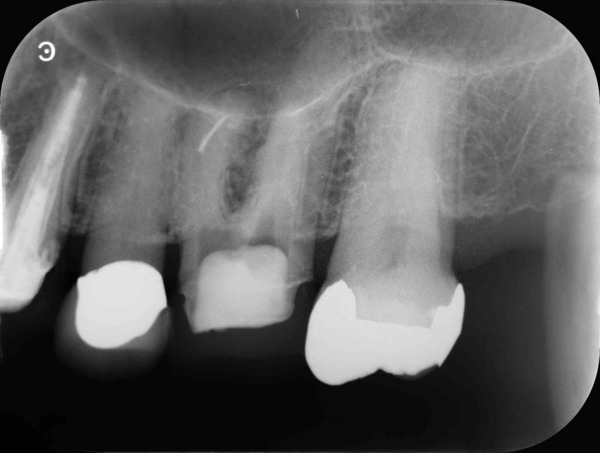

術前のレントゲン写真とお口の中の状態です。左上の前から6番目の歯(#26)です。

3本ある内の手前(近心)の根の中には治療用の器具が折れて残っていました。折れた器具が根管の中にあるだけでは問題になることは少ないですが、その先に感染がある場合は取り除いて治療をすることが望ましいです。

歯根の中の画像です。折れて残っている器具が確認できます。

根の中を詰めた直後のレントゲン写真です。